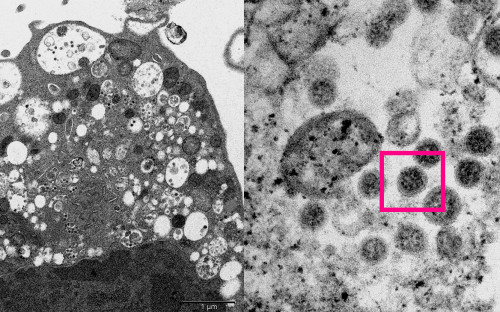

Последнее фото Мичио Хошино, известного японского фотографа дикой природы, который был растерзан медведем на просторах Камчатки 8 августа 1996 года .

«Последнее фото Мичио Хошино, известного японского фотографа дикой природы . У Мичио осталась жена и сын . А также множество великолепных фотографий, которые он успел сделать .

Гид предупредил фотографа об нависшей над ним опасности, объяснив, что зверь интересуется персонально Мичио . Наблюдая за работой Мичио, Ревенко заметил, что медведь нервничал . . .